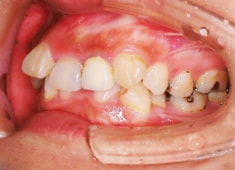

治療前

治療開始時